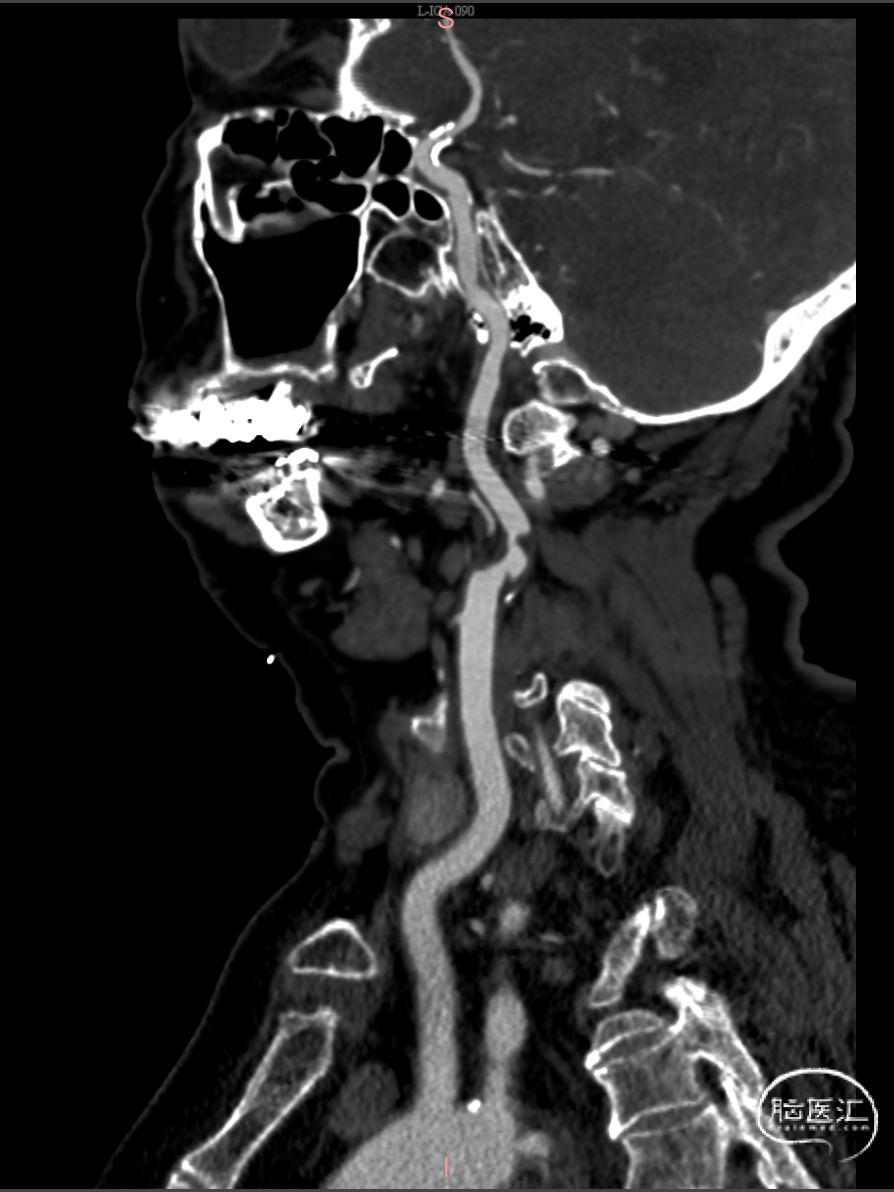

➢头颈部动脉CTA显示:

术前CTA提示:右侧颈内动脉起始段重度狭窄;右侧椎动脉起始段重度狭窄;左侧大脑中动脉M1段闭塞,脑梗死恢复期。

局麻下行“左侧颈内动脉C1段支架植入术”,常规消毒铺巾,1%利多卡因局部浸润麻醉后,采用改良seldinger技术行右侧股动脉穿刺,置入8F鞘。同轴技术下将8F导引导管超选至左侧颈总动脉造影,造影提示:左侧颈内动脉C1段重度狭窄伴溃疡斑块,狭窄率约80%。

造影提示:右侧颈内动脉C1段重度狭窄,狭窄率约90%。